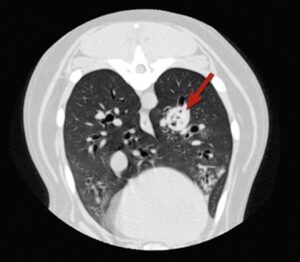

- Lungs are more complicated and may require specialist investigation and treatment in the form of a CT scan and removal using the flexible bronchoscope. Occasionally these cases may require major surgery to open the chest and remove an entire affected lung lobe

CT scans showing different views of the same dog’s chest with a grass seed lodged in the lungs (the grass seed is arrowed)